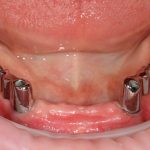

Рекомендации по установке имплантов. Для всех. Часть V.